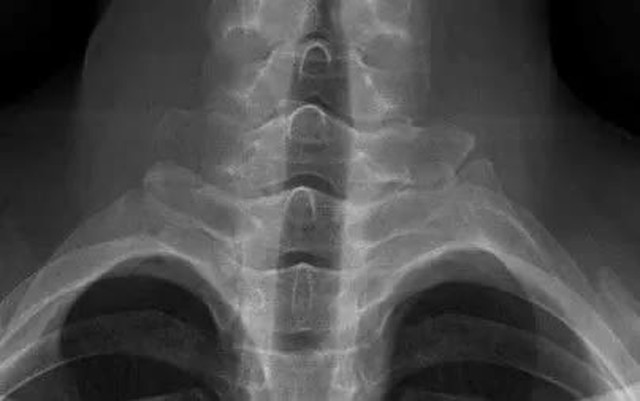

Thăm khám lâm sàng cho thấy bệnh nhân hạn chế nhẹ vận động cột sống cổ, không sưng đau các khớp ngoại biên. Chụp X-quang cột sống cổ chưa ghi nhận bất thường. Tuy nhiên, khi được chỉ định chụp X-quang khung chậu, các bác sĩ phát hiện viêm khớp cùng chậu độ III hai bên. Xét nghiệm miễn dịch cho kết quả HLA-B27 dương tính, các chỉ số viêm như CRP và tốc độ lắng máu đều tăng.

Dựa trên lâm sàng và cận lâm sàng, bệnh nhân được chẩn đoán viêm cột sống dính khớp thể trục theo tiêu chuẩn New York sửa đổi/ASAS 2009. Theo ThS.BSNT Nguyễn Mạnh Quyết, Khoa Khám chữa bệnh theo yêu cầu và quốc tế, Bệnh viện E, đây là trường hợp điển hình của bệnh viêm cột sống dính khớp ở người trẻ nhưng dễ bị bỏ sót do tổn thương giai đoạn sớm chưa biểu hiện rõ trên X-quang cột sống.